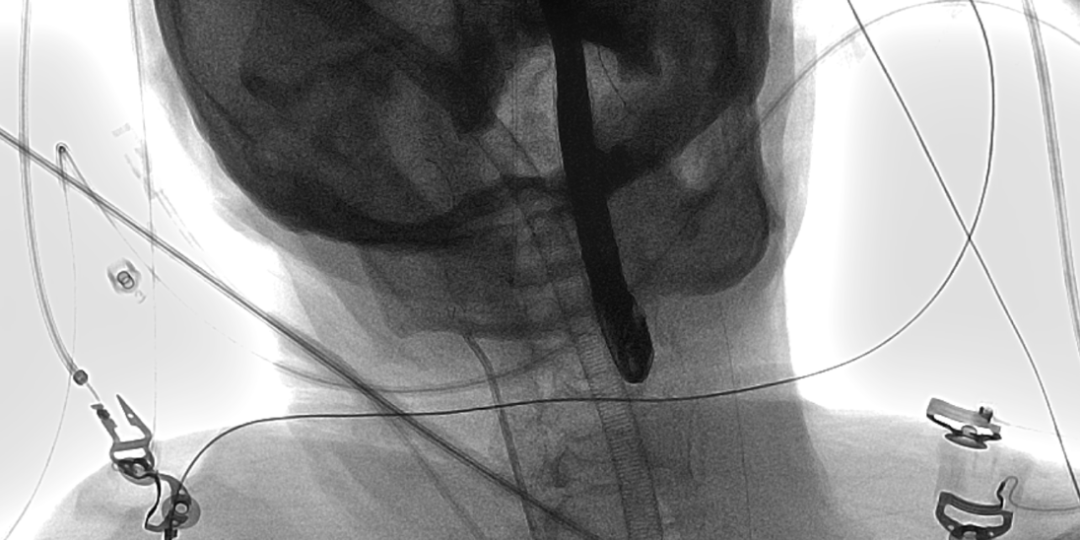

病例1 - 抗栓塞脑保护下 Type 1 型二叶瓣

男性,77岁,因“活动后胸闷气急半年”入院。既往有高血压病、心房颤动、左心耳血栓、脑卒中病史,CHA2DS2-VASc评分6分。

手术难点及策略:

该病例为Type-1 型二叶瓣,瓣环79mm,平均直径25.1mm,左右窦融合伴长条状钙化融合,预计不易扩开,拟23mm球囊预扩,植入TAV24 号 VitaFlow瓣膜。

手术过程:

23mm球囊预扩

(有腰征,无返流)

开始释放后再次定位

23mm球囊后扩

植入后造影

术后压差1mmHg

术中经食道心超评估:

人工主动脉瓣:植入深度 7mm,峰值流速1.2m/s,峰值压差6mmHg,平均跨瓣压差3mmHg,原左-右冠窦结合部微量瓣周漏。